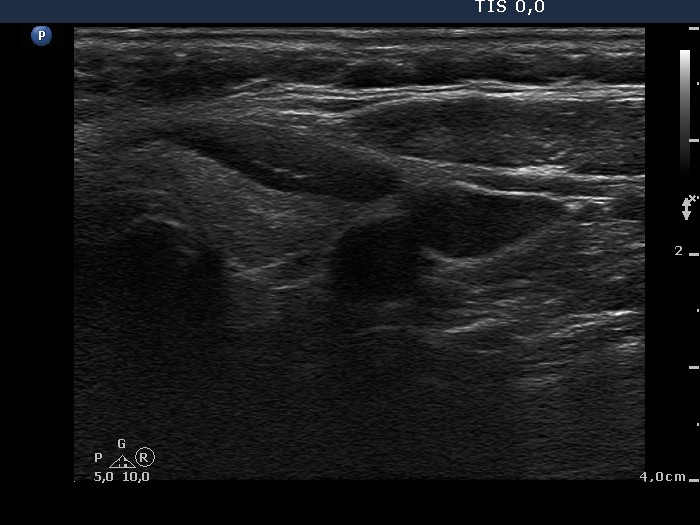

Ultrasonography. The thyroid was echonormal. There was a hypoechogenic nodule in the right lobe. The nodule displayed a halo sign and perinodular blood flow. There were smaller, moderately hypoechogenic areas within both lobes.

Combined cytological-clinical-sonographic diagnosis: Hashimoto's thyroiditis and Hürthle-cell tumor.

Histopathology disclosed Hashimoto's thyroiditis and Hürthle-cell adenoma.